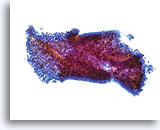

Biopsie

Papillär-seröses Endometriumkarzinom

Gleiche Patientin, gesplittetes Zellmaterial

Biopsie

Papillär-seröses Endometriumkarzinom

Gleiche Patientin, gesplittetes Zellmaterial